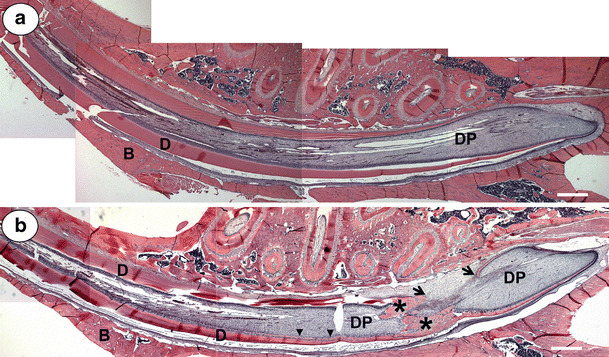

Figure 2a,b shows, respectively, parasagittal survey photo montages of S+F and Nx+F rat incisors. To determine the effect of Nx alone on incisor development, we compared incisors of the S group (Fig. 3a) with those of Nx animals (Fig. 3b). The most prominent effect seen in all uremic animals was widening of the predentin layer beginning with the earliest stages of dentinogenesis (Fig. 3b).

Fig. 2.

Parasagittal photomontage from sham-operated fluoride-treated (S+F) (a) and nephrectomized fluoride-treated (Nx+F) (b) specimens. The pulp chamber (DP) of the S+F specimen appears normal (a), whereas the Nx+F pulp chamber contains large amounts of osteodentin-like matrix (b, asterisks; see also Fig. 5b for details) and near the predentin layer (arrowheads; see also Fig. 5a for details). In addition, the cementum-related (root) dentin is discontinuous in the Nx+F specimen (black arrows). B bone, D dentin. (Bars = 1000 µm)